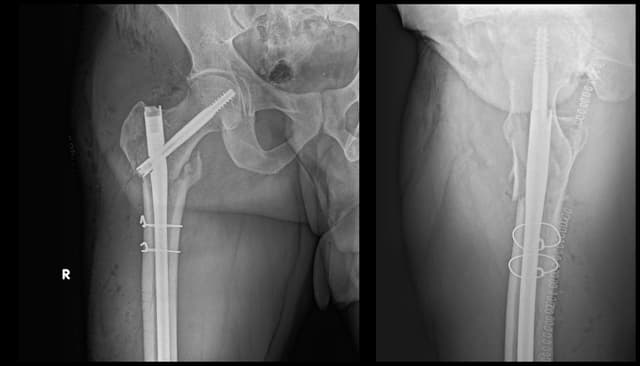

Subtrochanteric Femur ORIF

Post-op